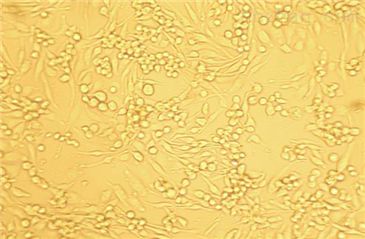

[HPAC细胞]人胰腺腺泡上皮癌

细胞生长:贴壁生长

细胞形态:上皮样